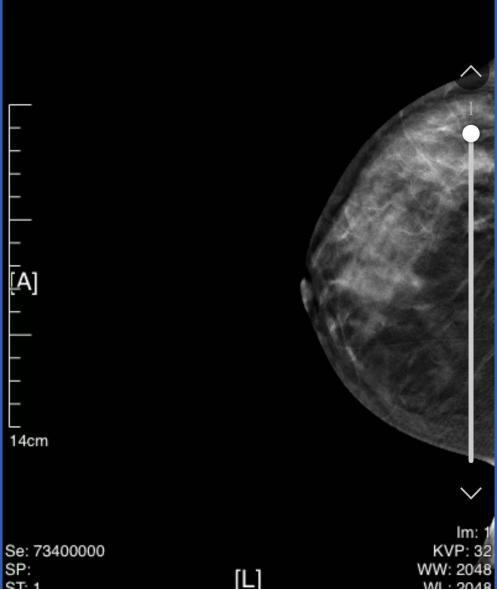

图1 乳腺彩超结果(2024-03-01)

1、双侧乳腺实质呈不均匀致密型。

2、右乳外上象限可见稍高密度肿块(断层所示CC位22/66、MLO位12/68),边缘分叶,大小约27mm*21mm。右乳外上象限可见多发细小多形性钙化灶。局部呈簇状分布。右乳中外象限似可见稍高密度小肿块(断层所示CC位33/66、MLO位21/68),长径约6mm。

钼靶提示:右乳外上象限肿块伴微钙化,右乳外上象限成簇状钙化灶,BI-RADS 4C类